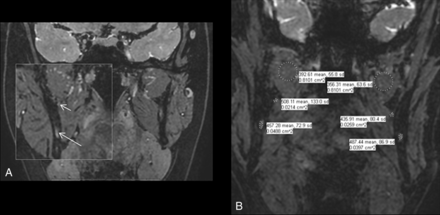

A, MIP coronal 3D PSIF image showing class II injury to the right IAN with mild increase in caliber (less than 50% of the left) and signal intensity of the right IAN (long arrow) in comparison with a normal left inferior alveolar nerve (short arrow). B, Sagittal reconstruction MIP 3D PSIF image showing increase in caliber and signal intensity of the right IAN (long arrow) proximal to injury site (arrowhead). C, Normal uniform caliber and signal intensity of the left IAN (short arrow).

A and B, MIP 3D coronal PSIF images show a hyperintense left LN (long arrow) with a 3-mm neuroma in continuity (demarcated by 3 arrowheads) compatible with class IV injury. C and D, Sagittal reconstructions show the abnormal left LN neuroma (demarcated by 3 arrowheads) compared with a normal right LN (short arrow).